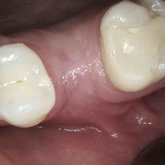

Porcelain crowns and restorations made in one appointment.

We make it a priority to incorporate the latest in dental technology in everything we do at our practice. ...